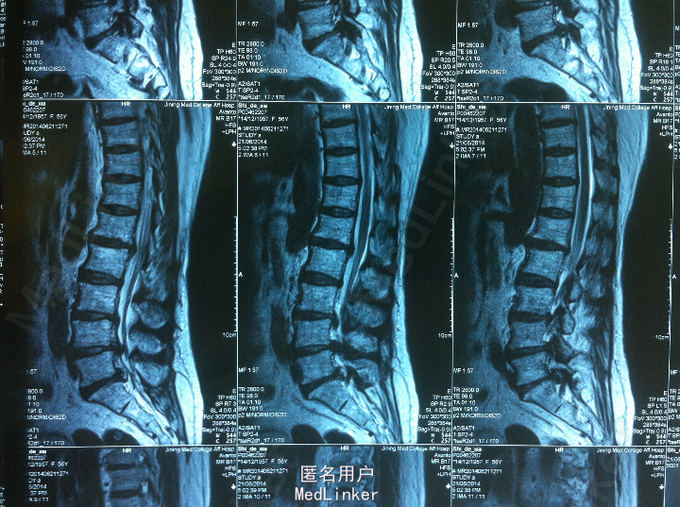

主诉、病史 腰痛10年,加重伴右下肢放射性疼痛、麻木2个月 患者10年前无明显诱因出现腰痛不适,不伴下肢放射性疼痛、麻木、无力。2个月前无明显诱因出现腰痛加重,伴左下肢放射性疼痛、麻木,腰腿活动受限,无纳差、消瘦。

查体:腰部叩痛,腰部活动受限,左侧小腿外侧、足背感觉减退,左侧踝背伸、踇背伸、跖屈肌肌力4级,右侧踝背伸、踇背伸、跖屈肌肌力4-5级,双侧膝腱反射+,跟腱反射+,双侧巴氏征阴性。辅助检查: X-ray:腰椎退行性变节段性不稳。CT:腰椎间盘突出,腰3/4,4/5,腰5/骶1, MR:腰椎间盘突出,腰3/4,4/5,腰5、骶1椎间盘突出。

诊断:腰椎间盘突出症并节段性不稳 处理: 1、完善相关辅助检查,明确诊断,有无手术指证; 2、完善手术评估,有无手术禁忌,手术风险并发症; 3、在全麻下行腰椎后外侧入路选择性减压、横突间植骨融合内固定术